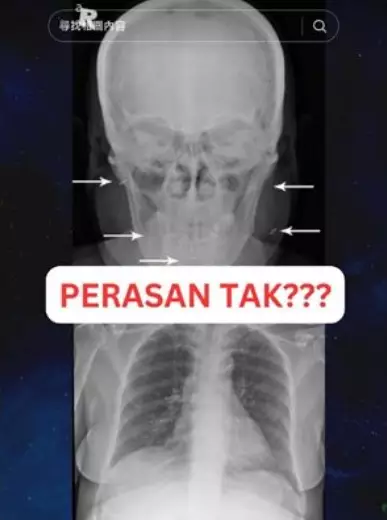

病人身上有4根「魅力針」。TikTok截圖

病人身上有4根「魅力針」。TikTok截圖

當醫院為她做諸如血液、CT和照X光時,竟然意外發現這名女病患的眼睛、臉部、頸部還有胸部等4個部位都植入了民間俗稱「魅力針」的巫具。事實上,魅力針又稱charm needle,是印尼一種名為Susuk的民間巫術,巫師會將金屬細針植入身體軟組織內,並宣稱有美容、治療疾病等效果,因此很受歡迎。

病人身上有4根「魅力針」。TikTok截圖

為了進一步醫治,病人的魅力針需要被拔除,但直到她死前一刻她仍不願意,這導致拉茲夫如今回想起來都覺得非常可惜,對當時未能將實情告知病人家屬深感後悔,「我不知道是什麼毒害了她的思想,但這件事她的孩子們肯定不知道,我也沒法透露給他們」。